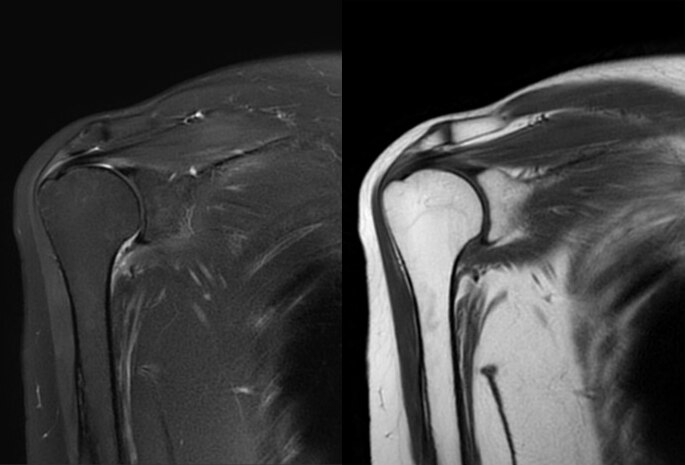

前機種のMRIは寝台が固定式でしたので、患者が汎用ストレッチャーで検査に来た場合、専用ストレッチャーに乗り換えた後MRI室へ入室し、その後さらにMRIの寝台へ移動を行っていました。現在は、脱着式の寝台であるeXpress Dockable Tableを使用することにより、患者を汎用ストレッチャーから直接MRIの寝台へ移動することが可能となりました。患者の移動に費やす作業が2回の行程から1回の行程になったことで、患者入れ替えに掛かる時間が短縮しました。また、MRI検査スタッフ以外の職員が患者移動のために撮影室に入室することが無くなったので所持品の吸着事故が発生していません。

今回、脱着式寝台を初めて使用しますが、脱着時の手順についてはガントリー上部のモニターに表示される手順ガイドを確認しながら操作しています。

図1 脱着式寝台

(赤丸:脱着操作時にガントリーモニタに表示される手順ガイド)